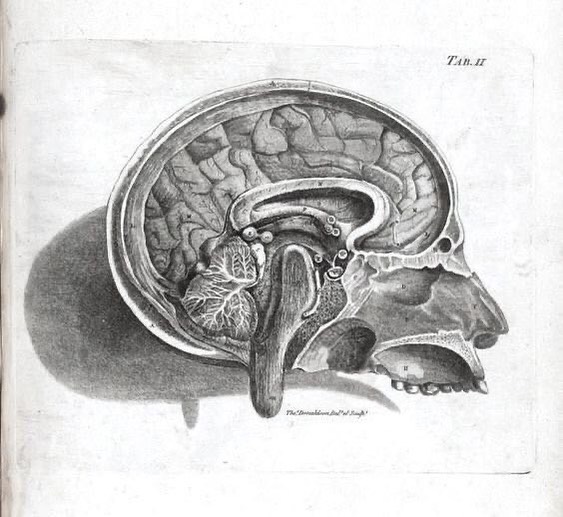

Camillo Golgi received the 1906 medicine prize for discovering nerve cells could be stained with silver nitrate. This enabled Golgi and other researchers to make detailed studies of our nervous system, such as the ones pictured. Learn more: bit.ly/2WxPIs3

Camillo Golgi received the 1906 medicine prize for discovering nerve cells could be stained with silver nitrate. This enabled Golgi and other researchers to make detailed studies of our nervous system, such as the ones pictured.

Learn more: bit.ly/2WxPIs3